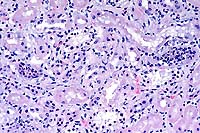

- Case 22-1. Lung. Alveoli are filled with neutrophils

and lined by type II pneumocytes which occasionally contain eosinophilic

intranuclear inclusions bodies.

- Case 22-1. Lung. A syncytial giant cell is accompanied

by abundant foamy alveolar macrophages within and thickening

the septal walls (interstitial pneumonia).